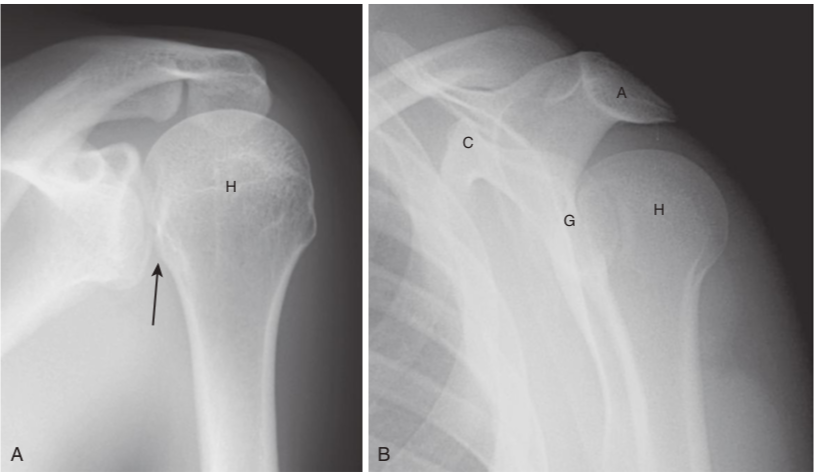

Posterior dislocation of the shoulder.

Posterior dislocations of the shoulder are much less common than anterior dislocations, but more difficult to diagnose. On the frontal view (A)look for the humeral head (H) to be persistently fixed in internal rotation and resemble a lightbulb, no matter how the patient turns the forearm. There is also an increased distance between the head and the glenoid (black arrow). B,On the Y-view, the head (H) will lie under the acromion (A), a posterior structure of the scapula, not the anteriorly located coracoid process. (C). G,Glenoid.